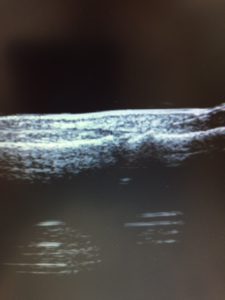

足に物を落とし、指を腫らして来院した患者さんです。

超音波で見た所、異常画像が描出されました。

骨折を疑い整形外科の先生にご高診いただいたところ

骨折が確認されました。